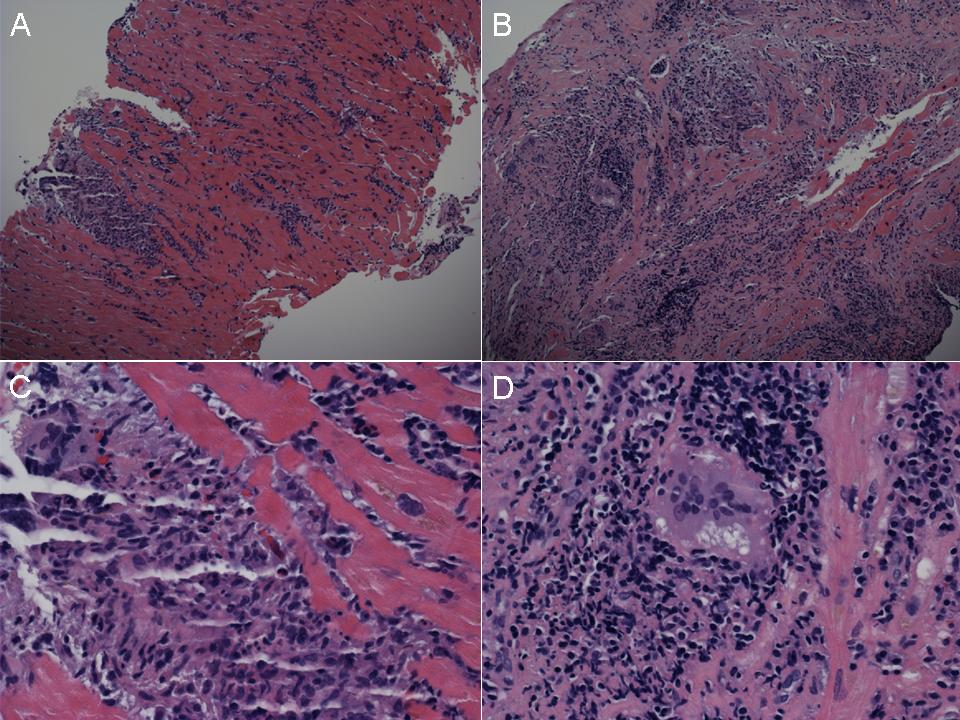

Межуточный миокардит: гистологические исследования

Раздел: Идеи и советы